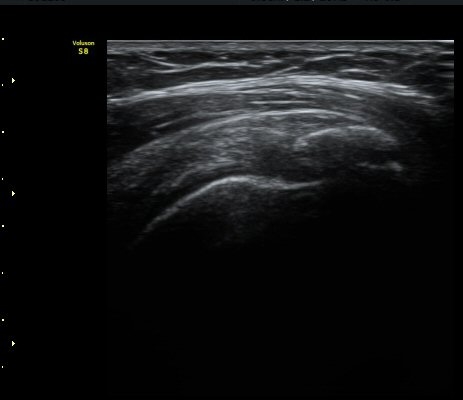

¾î±ú¸¦ 90µµ ¿ÜÀüÇÑ »óÅ¿¡¼­ À­ÆÈÀ» ³»È¸ÀüÇÏ´Ï °ßºÀ¿À±¸µ¹±â Àδ밡 Ç¥ÃþÀ¸·Î

ÀüÀ§µÈ´Ù(÷ºÎ ÆÄÀÏ µ¿¿µ»ó 1)